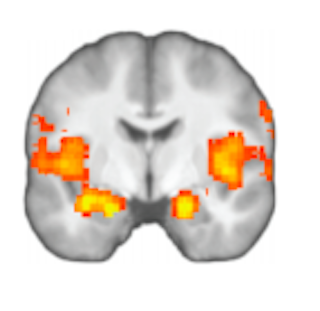

Kävi ilmi, että on olemassa hyvä syy siihen, miksi ihmiset ovat kiinnostuneita onnellisista lopuista. Aivotallenteiden laskennalliset analyysit osoittivat, että rekisteröimme kokemuksen arvon kahdella eri aivoalueella. Kokonaisarvo koodataan amygdala-nimiselle aivoalueelle, jolla on ristiriitainen maine. On väitetty, että amygdalan aktivaatio välittää tunnereaktioita, jotka voivat johtaa irrationaaliseen käyttäytymiseen, mutta on myös osoitettu, että se voi koodata rationaalisesti taloudellisten säästöstrategioiden lopputuloksen.

Mutta amygdalan vaikutusta päätöksentekoon hillitsee lannistava aktiivisuus anterior insula -nimisellä alueella, jos aiempi kokemus ei pääty hyvin. Anterior insula liittyy toisinaan negatiivisten kokemusten, kuten inhon, käsittelyyn – mikä viittaa siihen, että jotkut ihmiset ovat aktiivisesti vastenmielisiä onnettomasta lopusta.

Pelikokeessa hyvät päätöksentekijät valitsivat ne potit, joissa oli yhteensä eniten rahaa, riippumatta siitä, saivatko he lopussa suurempia kultakolikoita. He osoittivat kokonaisarvon vahvaa representaatiota amygdalassa, kun taas suboptimaalisilla päätöksentekijöillä oli voimakkaampaa aktiivisuutta anteriorisessa insulassa. Toisin sanoen hyvien päätöksentekijöiden on kyettävä kumoamaan kokemuksen epämiellyttävä vaikutelma, kuten onneton loppu.